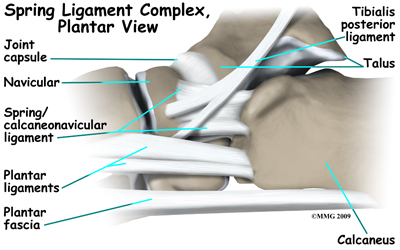

Many small ligaments hold the bones of the foot together. Most of these ligaments form part of the joint capsule around each of the joints of the foot. A joint capsule is a watertight sac that forms around all synovial-type joints. The capsule is made up of the ligaments around the joint and the soft tissues between the ligaments that fill in the gaps and form the sac.

The spring ligament complex is often involved in AAFD. This group of ligaments supports the talonavicular joint. The spring ligament complex works with the posterior tibial tendon and the plantar fascia to support and stabilize the longitudinal arch of the foot.